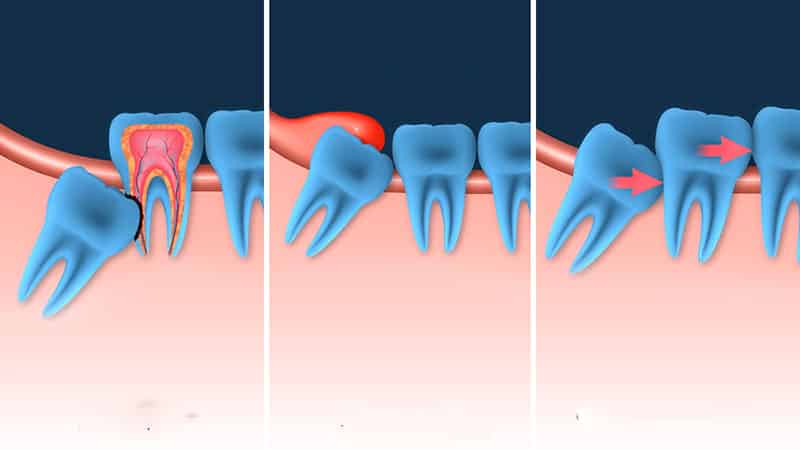

Теоретически, зубы мудрости, или восьмерки, являются полноценными зубами, как и остальные. Многие люди ошибочно полагают, что они недоразвиты, даже сомневаясь в наличии нерва в этих зубах. Однако это мнение является неверным. По своей структуре и функции моляры мудрости не отличаются от других зубов. Основная проблема заключается в их неправильном росте, который часто возникает из-за позднего появления восьмерок, когда кости лица уже полностью сформированы, и альвеола не может их вместить.

Эта ситуация может привести к искривлению верхней части зуба. Часто встречаются случаи, когда восьмерка вырастает горизонтально или под значительным углом к челюсти. Такие ситуации требуют немедленного хирургического вмешательства. Игнорирование проблемы может привести к дополнительным осложнениям с седьмым моляром.

Кроме того, корни зуба мудрости могут деформироваться в процессе своего развития, что может повредить челюсть или привести к их сращиванию. Медленное появление восьмерок также может стать причиной кариеса и даже частичного разрушения как самого зуба мудрости, так и соседнего седьмого моляра. Обычно все эти проблемы возникают из-за позднего появления зуба, когда костная ткань теряет свою пластичность, и ширина челюсти не позволяет зубу нормально прорезаться.